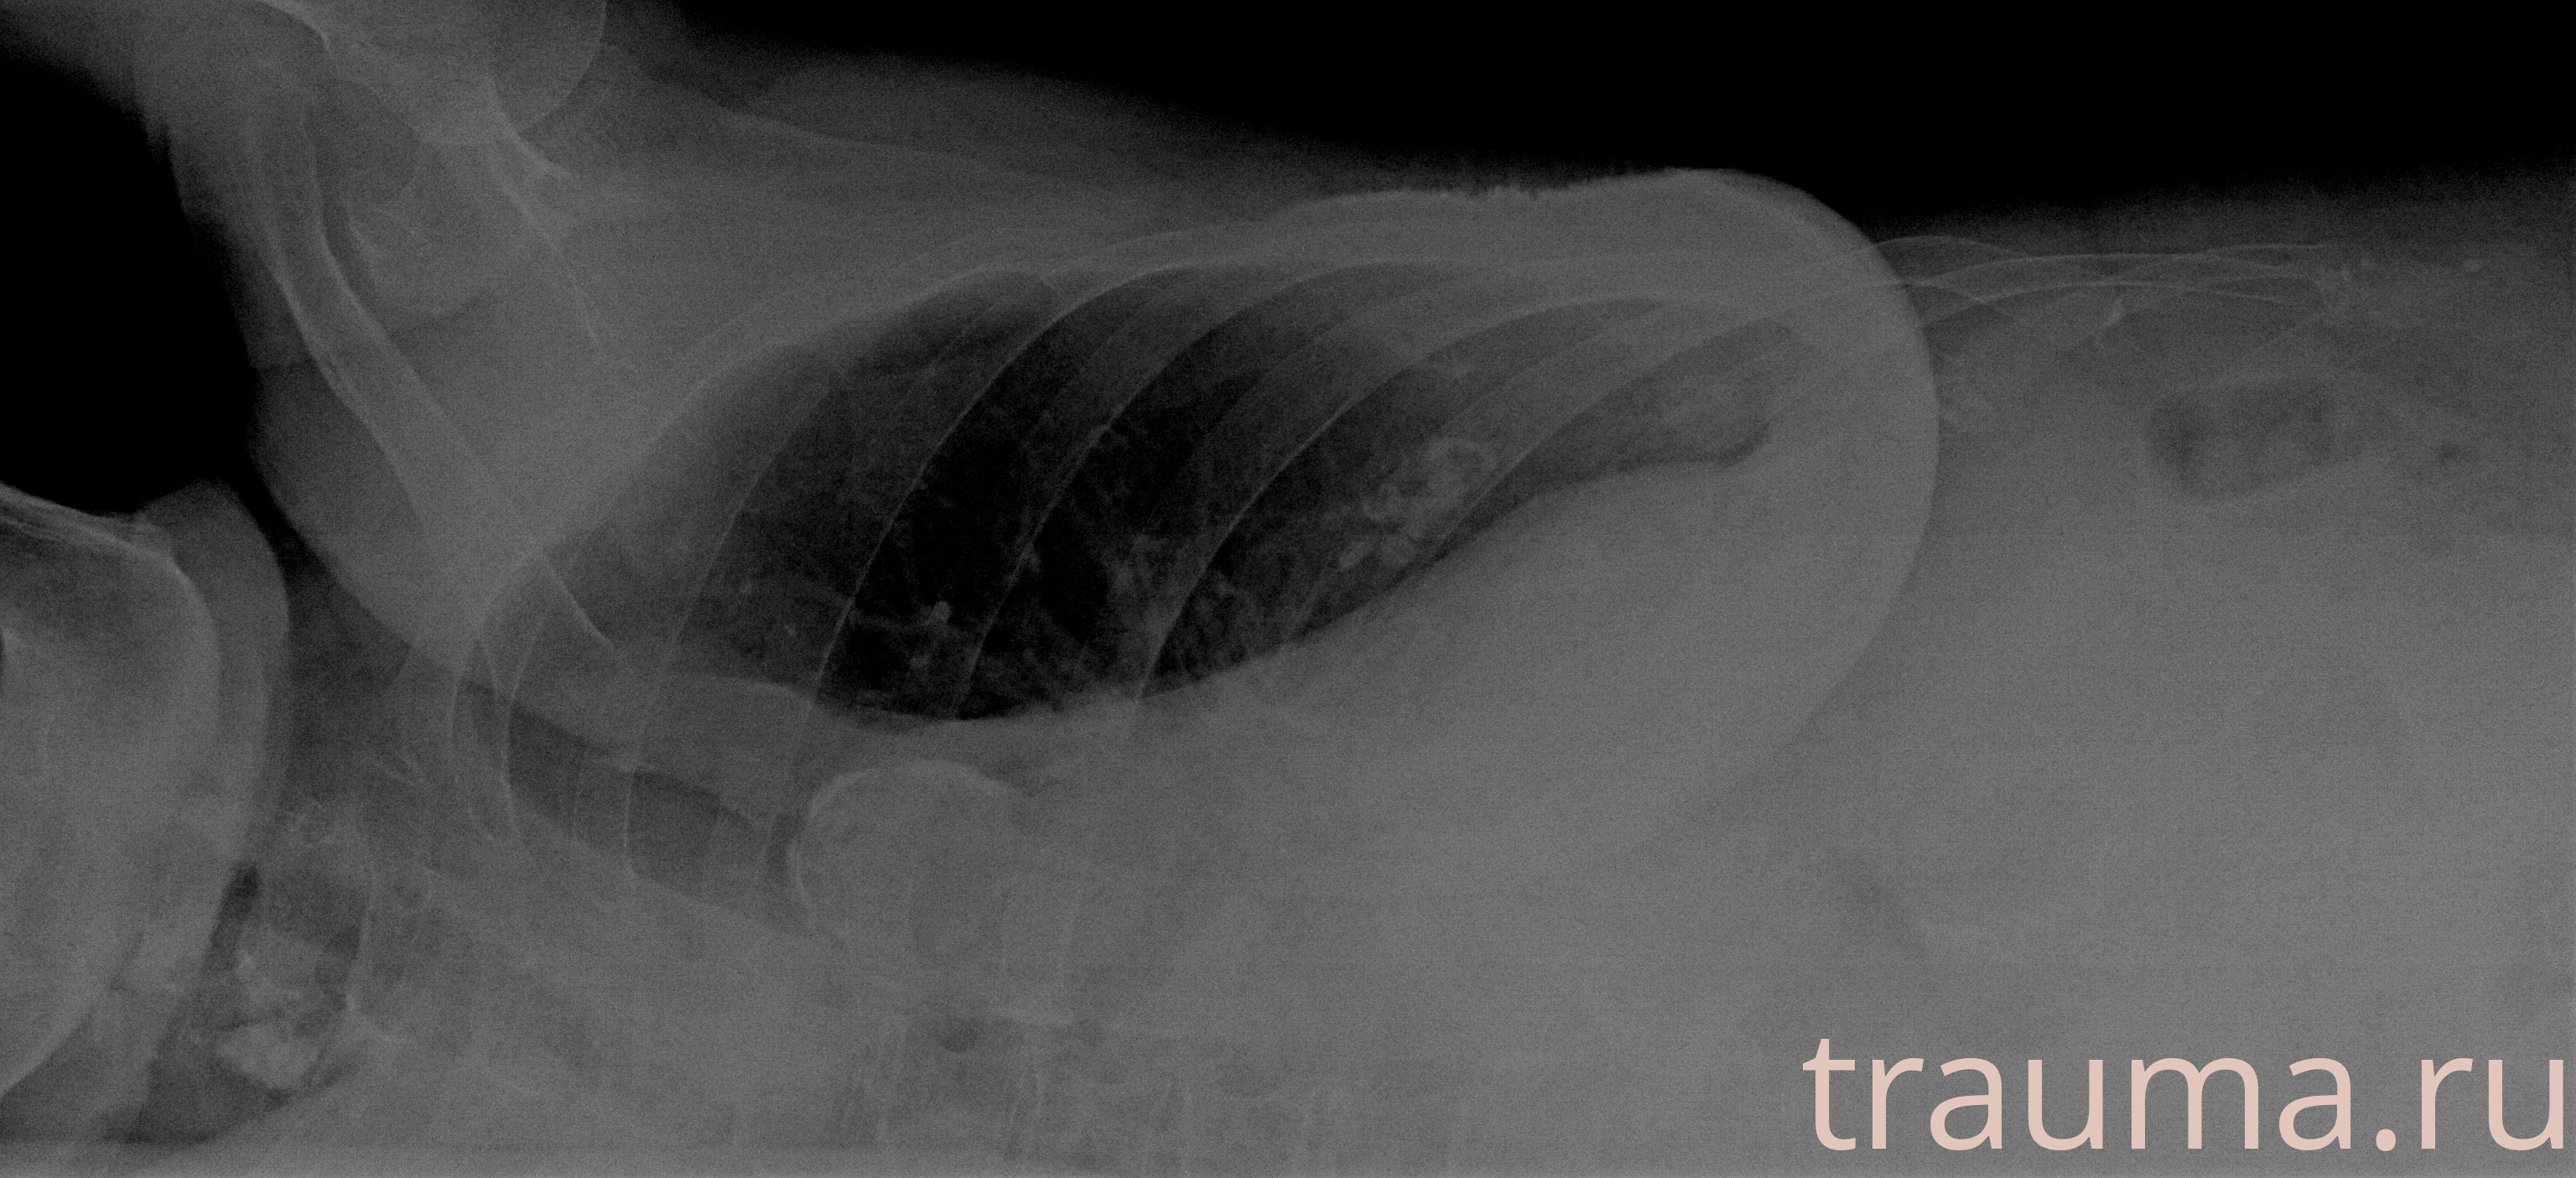

Рентгенограммы

Рентген на дому: по вашему адресу приезжает врач-рентгенолог, травматолог-ортопед с мобильным рентгеновским аппаратом, проводит диагностику травмы или заболевания, делает необходимые рентгенограммы, дает рекомендации по дальнейшему лечению. Получить качественные снимки в домашних условиях возможно благодаря уникальной методике, разработанной МосРентген Центром для института  Склифосовского

при переломе шейки бедра и пневмонии от компании МосРентген Центр - партнера Института имени Склифосовского